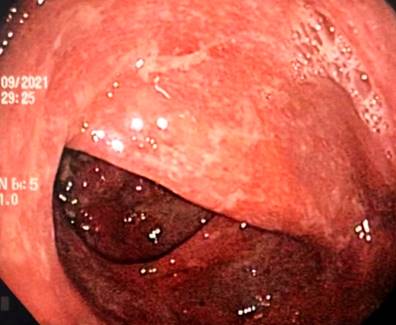

A 43-year-old female patient with a medical history of ankylosing spondylitis (AS) since the age of 20, fibromyalgia, arterial hypertension, hypothyroidism, and latent tuberculosis treated in 2019 presented to the hospital with symptoms of diffuse abdominal pain and multiple bloody diarrheal stools (more than fifteen times a day) for a week. The patient had been treated with etanercept, adalimumab, abatacept, and since 2017, with secukinumab. On admission, the patient was tachycardic, dehydrated, afebrile, and had lower abdominal pain without signs of peritoneal irritation. Laboratory tests showed no alterations in blood count, and an ultrasound and tomographic study revealed wall thickening of the right colon with mucous enhancement, multiple mesenteric lymphadenopathies, and some free fluid at the bottom of the sac (Figure 1). Colonoscopy showed edema, erythema, mucosal friability, loss of vascular pattern, and ulcerations covered by fibrin from the rectum to the cecum, which are consistent with extensive ulcerative colitis (Figure 2 ).